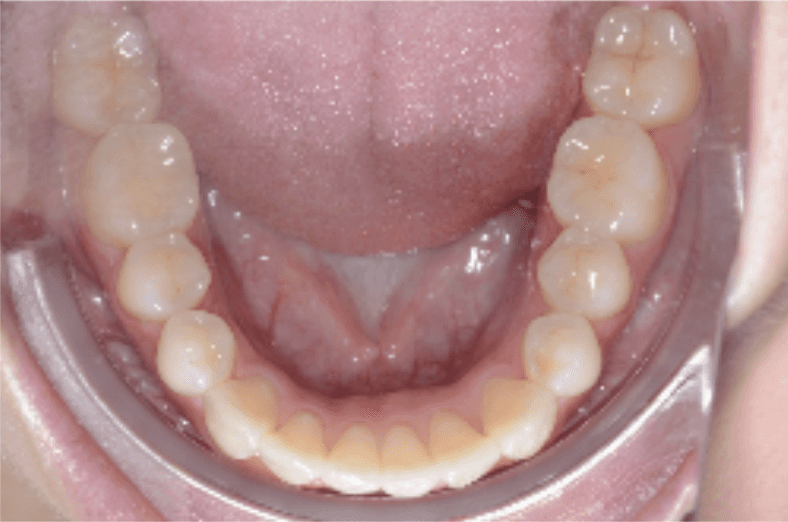

Initial treatment

INTRAORAL